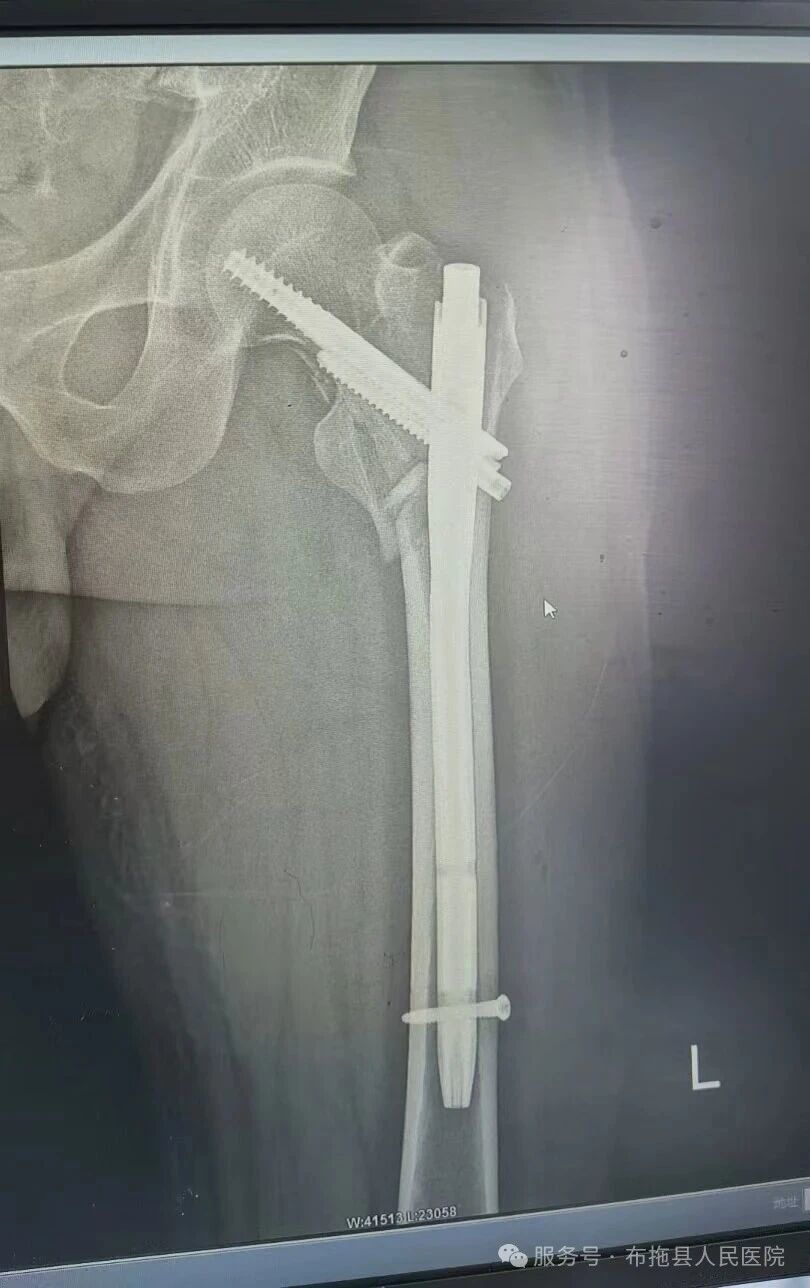

for (var i = 0,len = adKeys.length; i 在多數人認知里,股骨粗隆間骨折是高齡老人的“人生最后一次骨折”,可當這種骨折以更復雜的“粉碎性”模樣降臨在年輕人身上,碾碎的不僅是骨骼,更是一個家庭的支柱與未來的希望。近日,布拖縣人民醫院骨科的一臺手術,不僅重塑了一位患者的人生,更填補了當地醫療技術的空白——這背后,是一場從東海之濱到川西高原的醫者仁心接力。 意外突襲,高原上的家庭困境 “醫生,我還能站起來嗎?家里不能沒有我干活啊……”骨科診室里,年輕患者的聲音帶著顫抖與無助。不久前,他因意外受傷導致左髖部劇烈疼痛、無法活動,被緊急送往我院。X光片清晰顯示:左側股骨粗隆間粉碎性骨折,骨折端錯位明顯。 這個消息像一塊巨石壓在骨科主任潘雄的心上。作為家庭的頂梁柱,患者的康復直接關系著全家的生計。可傳統治療方案都有明顯局限:保守治療需長期臥床,并發癥叢生,對年輕患者而言等同于喪失生活質量;切開復位鋼板內固定術創傷大、出血多,對粉碎性骨折的固定效果也不盡理想。就在一籌莫展之際,潘雄想到了正在醫院開展“東西部協作”醫療幫扶的慈溪專家——勞錦錦副主任醫師。 千里馳援,“Intertan”帶來生機 來自慈溪市中醫院骨科的勞錦錦副主任醫師,在髖部骨折微創治療領域有著豐富經驗。他仔細研判患者病情后,提出了一個在沿海地區成熟、但高原山區尚未開展的手術方案:閉合復位Intertan髓內釘內固定術(是一種用于治療股骨轉子間骨折的內固定裝置,其設計結合了生物力學優勢與穩定性,尤其適用于不穩定型骨折)。 “對年輕患者,我們的目標不只是愈合,更是讓他重歸勞動與生活。”勞醫師解釋道,這項技術有兩大核心優勢: ? 微創保護:采用“閉合復位”方式,僅在皮膚開幾個小切口,不暴露骨折端,如同“打地道戰”般保護骨折處血供,為愈合創造黃金條件。 ? 堅強固定:獨特的雙釘系統能形成“交叉鎖死”結構,為粉碎骨折提供穩固支撐,允許患者早期下地,規避長期臥床的致命并發癥。 方案讓骨科團隊既振奮又緊張:振奮的是患者有了最佳選擇,緊張的是這是醫院首例,從器械熟悉到手術配合都是全新挑戰。 無影燈下,首例手術的攻堅時刻 手術室里,氣氛凝重而有序。在勞錦錦醫師的主導與“手把手”指導下,醫療團隊展開了精密協作: 1. 精準定位:借助C型臂X光機透視,鎖定微創入口點,毫厘之差關乎成敗。 2. 巧妙復位:通過牽引床與專業手法,將粉碎的骨折塊間接復位,考驗著醫者的經驗與手感。 3. 髓內“架橋”:主釘順利植入股骨髓腔,如同在骨骼內部架起堅固的“大梁”。 4. 鎖定核心:雙釘系統精準打入股骨頭頸部,屏幕上出現完美的“交叉鎖死”結構,粉碎骨折區域被牢牢固定。 當確認固定成功的那一刻,手術室里所有人都松了口氣。整臺手術出血量極少,用時比預期更短,圓滿成功。而這場手術更是一堂鮮活的教學課——勞醫師全程講解步驟要領與風險要點,將技術與理念同步傳遞。 授人以漁,留下“帶不走的醫療隊” “醫療幫扶的核心不是‘我來做’,而是‘我教會你做’。”勞錦錦醫師的話,道出了東西部協作的真諦。 術后恢復遠超預期:第二天患者便能在協助下坐起,一周后已能扶著助行器下地站立。看著髖部小小的切口和逐漸恢復的活動能力,患者與家屬的臉上終于露出了久違的笑容。 “這是我院骨科發展的里程碑!”我院院長感慨道,“它讓布拖百姓在家門口就能享受到東部先進醫療技術,更留下了寶貴的診療理念。” 骨科主任潘雄也深有感觸:“我們學到的不僅是手術技巧,更是面對復雜病情的臨床思維與挑戰信心。現在,我們有底氣獨立開展這項技術了!” 從“首例”到“常態”,守護高原健康 一例手術,改寫一個患者的人生;一項突破,開啟一個科室的新篇;一次幫扶,連接起跨越山海的情誼。 這場跨越2600公里的“髓”心接力,正是“東西部協作”的生動實踐。它見證著優質醫療資源不斷下沉的足跡,更守護著高原百姓的健康希望。布拖縣人民醫院骨科正以此為起點,在守護一方安康的道路上,留下愈發堅實的印記。 勞錦錦 從事骨科工作十余年,畢業于浙江中醫藥大學,浙江大學在職研究生,曾于上海市第六人民醫院骨科進修學習,擅長四肢復雜骨折脫位的手術及保守治療,脊柱微創治療,髖關節置換等。 來源:布拖縣人民醫院公眾號